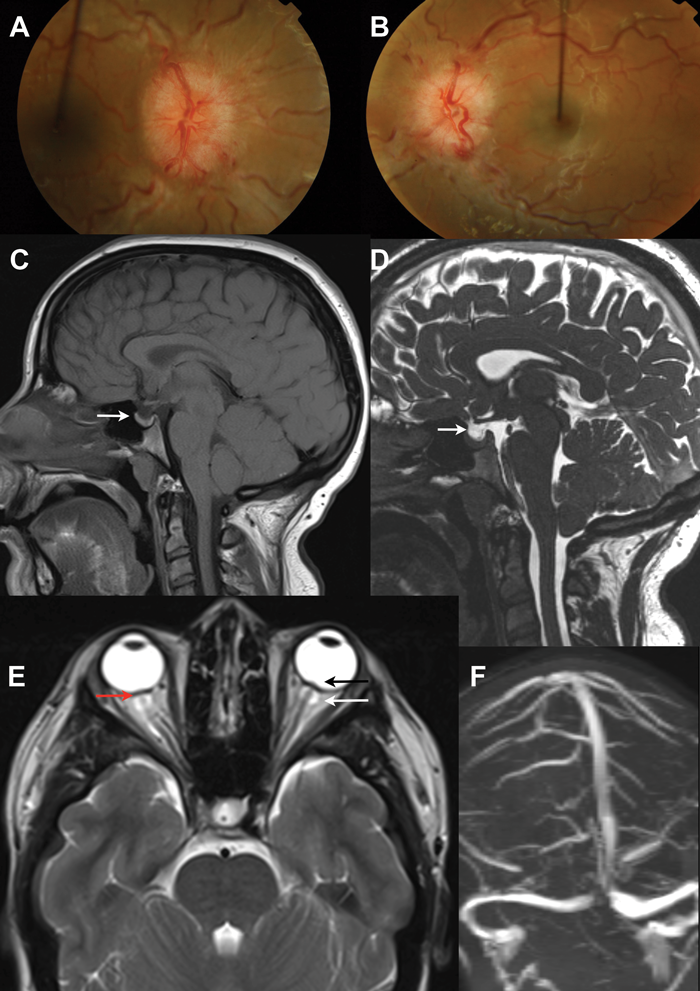

IIH occurs predominantly in women and although the underlying pathogenesis is not fully understood, it has a prominent association with obesity [2]. The condition is well known to ophthalmologists as the majority of patients typically present from their opticians or directly to the eye casualty with headaches and papilloedema (Figures 1A and B). Other symptoms may include blurred vision, visual obscurations, pulsatile tinnitus and double vision: none of which are pathognomonic for IIH [3]. The papilloedema is investigated urgently with neuro-imaging (Figures 1C-F) and lumbar puncture (LP) [4]; where there is raised LP opening pressure and if no underlying cause is found the patient is diagnosed with IIH [5].

Figure 1:

1A and 1B show colour fundus photos of bilateral disc swelling secondary to raised intracranial pressure (papilloedema).

The neuro-imaging features are non-specific and not diagnostic of IIH:

1C and 1D show MRI T2 and T1 sagittal images showing a partially empty sella.

1E is MRI showing distension of optic nerve sheaths (white arrow), flattening of the posterior globes (red arrow) and optic nerve head protrusion (black arrow).

IF is MR venography showing no cerebral sinus thrombosis.

The diagnostic criteria for IIH have evolved but retain the framework of the original criteria proposed by Dandy in 1937, through the modified Dandy criteria, to the updated modified Dandy criteria (Table 1) [7]. These revised criteria emphasise the need to exclude secondary causes of elevated ICP and the need for reliable cerebrospinal fluid (CSF) pressure measurement. An accurate diagnosis of IIH is dependent on neuroimaging that excludes space occupation, hydrocephalus and cerebral venous sinus thrombosis. There are several neuroimaging changes that are associated with raised ICP including empty sella (Figures 1C and D), distension of optic nerve sheaths (Figure 1E, white arrow), vertical tortuosity of the optic nerves and flattening of the posterior globes (1E, red arrow) and protrusion of the optic nerve head (Figure 1E, black arrow), but all of these are non-specific and not diagnostic of IIH.

Diagnosis is also dependent on a CSF opening pressure of >25cm CSF performed in the later decubitus position. CSF of 10-25cm represents the 95% reference interval for opening pressure in normal subjects and opening pressures of 30cm CSF or higher may be observed in normal subjects. CSF opening pressure can be influenced by body position, therefore the lateral decubitus position is recommended. The neuroimaging (Figures 1D-F) and CSF opening pressure specifications in the revised modified Dandy criteria should improve diagnostic accuracy and standardise recruitment for clinical trials in IIH.

All patients with papilloedema should be investigated with MR or CT venography to exclude cerebral venous sinus thrombosis (Figure 1F). Improvements in venography imaging studies now detail that many, if not all, with IIH have anatomical abnormalities of the cerebral venous sinus system. These include stenosis of the dominant or transverse sinus. What is not fully known is whether the stenosis result from intrinsic dural sinus anatomy or extrinsic compression by the increased intracranial pressure. Importantly, reducing ICP can lead to resolution of stenosis in most. The degree of stenosis does not appear to uniformly correlate with ICP or visual loss [17]. Neurovascular stenting has been reported, in a number of series, to lead to an improvement in symptoms and signs of intracranial hypertension.